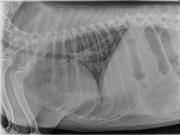

This week’s case is a 4-year-old female neutered Labrador Retriever with fever of unknown origin. What are your findings?

VD Abdomen

Abdomen: The abdomen is distended and there is poor peritoneal detail. The liver and spleen are enlarged with rounded borders. The colon is moderately dilated with gas. The small intestine appears normal. The urinary tract is not well visualized.

Bicavitary effusion may be due to round cell neoplasia, metabolic, or inflammatory disease. The hepatosplenomegaly is most suggestive of lymphoma. Differential diagnoses for the pulmonary pattern include lymphoma and non-cardiogenic pulmonary edema.

Hepatosplenic large granular cell lymphoma (NK type). The lungs were affected by pulmonary edema.